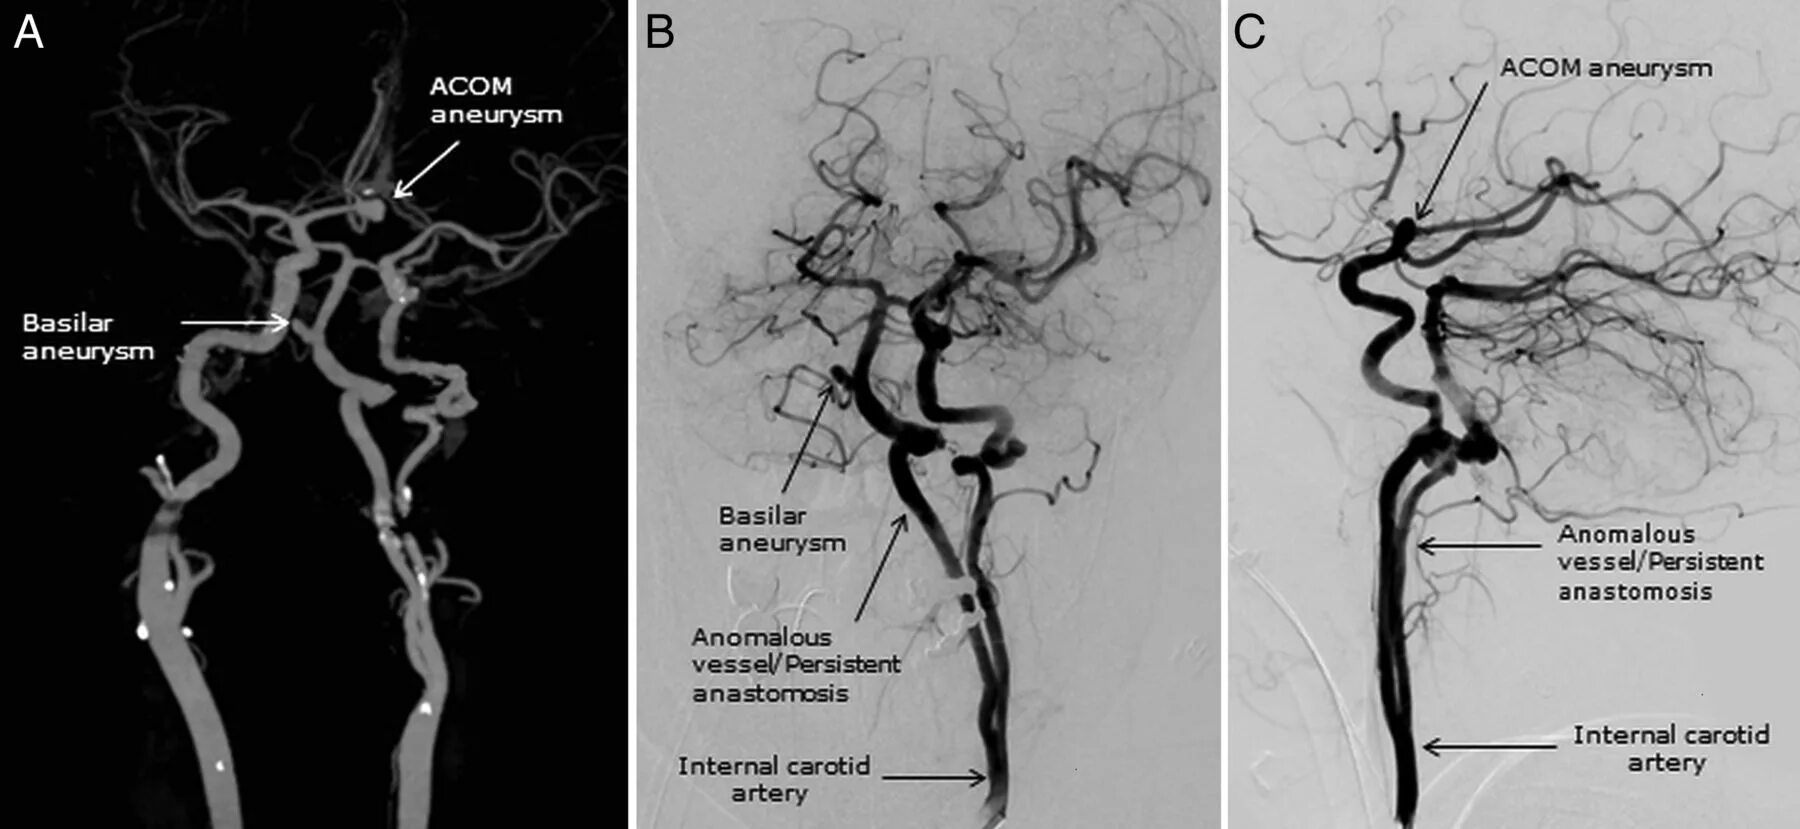

Интракраниальные сегменты